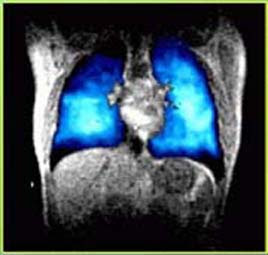

LUNGS MRI